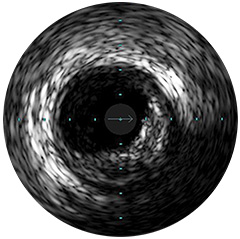

Figura 2

Digital IVUS imaging

Presentamos la nueva plataforma de aplicaciones intervencionistas Philips IntraSight, en la que la imagen, la fisiología, el corregistro* y el software se unen para facilitar una atención óptima del paciente. IntraSight ofrece un conjunto completo de modalidades clínicamente probadas, como la iFR/FFR, la IVUS y el corregistro* para simplificar las intervenciones complejas, acelerar los procedimientos rutinarios y proporcionar una mejor atención al paciente.